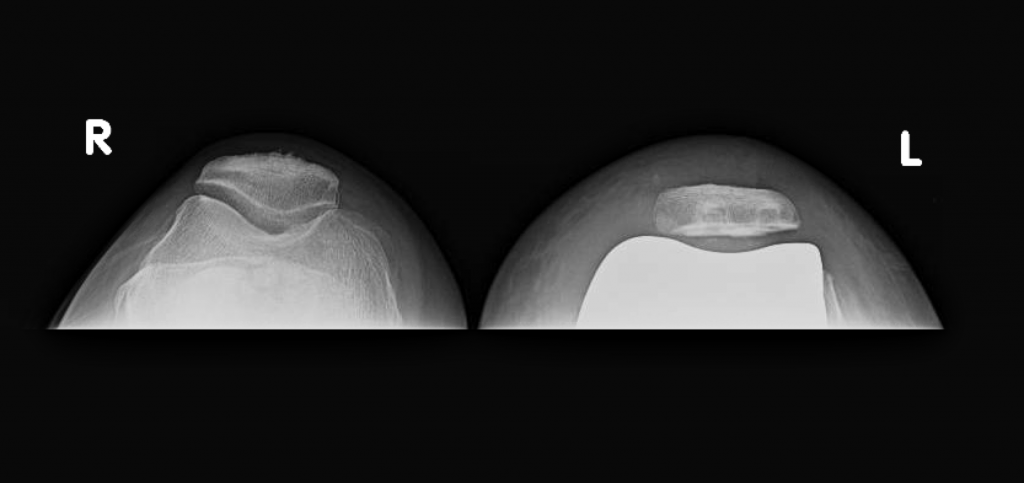

The patient’s customized surgical plan and individualized implants were created specifically for her based off of a CT scan of her knee.

At her 2 week postoperative visit, she was walking with a cane only for long distances and had a range of motion of 0-115.